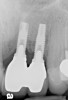

Clinical examination showed 2 mm of buccal recession with a shallow vestibule and absence of keratinized attached gingiva against the crown with 8 mm of circumferential pocketing accompanied by bleeding upon probing (Figure 15 and Figure 16). A periapical radiograph showed a symmetrical vertical osseous defect causing the loss of 50% of the bone around the implant (Figure 17). Because the patient had made a significant investment of time and finances to replace her lost tooth with the implant, she desired that the implant and restoration be retained, if feasible.

Fig 17. Radiograph showed symmetrical infrabony defect affecting 50% of the implant surface.

Figure 17